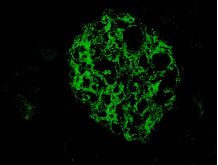

Bio SB has developed a highly sensitive Immunofluorescence and non-biotin monovalent Fab micropolymer IHC detection systems for the detection of IVD antibodies for Complement (C1q, C3c, C3d, C4c, C4d), Serum Proteins (Albumin and Fibrinogen) and Immunoglobulins (IgA, IgD, IgE, IgG, IgM, Kappa and Lambda) related to autoimmune conditions. Our innovative IF and IHC detection systems and high affinity antibodies, have opened the doors for a faster and accurate Immunofluorescence and Immunohistochemistry applicable to Autoimmune Disease like Nephropathies and Lupus.

These antibodies and detection systems are intended for use in Immunohistochemical (IHC) and Immunofluorescence (IF) applications of formalin-fixed paraffin-embedded tissues (FFPE), frozen tissue sections and cell preparations.

InDirect Immunofluorescence Detection

Rabbit FluoroDetector FITC |

Rabbit FluoroDetector FITC with FluoroMounter |

Rabbit FluoroDetector FITC with FluoroMounter with DAPI |